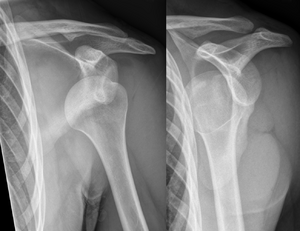

Dislocated shoulder X-ray 10.png

خلع أمامي للكتف الأيسر.

عادة ما يحدث خلع الكتف نتيجة لسقوط الشخص على ذراعه وهي ممدودة أو سقوطه على الكتف.[4] عادة ما يعتمد التشخيص على العلامات الظاهرة على الحالة ويتم التأكد عن طريق التصوير بأشعة إكس.[2] تصنف حالات خلع الكتف إلى خلع أمامي، خلفي، سفلي، وعلوي والأكثر شيوعاً هو خلع الكتف الأمامي.[2][1]